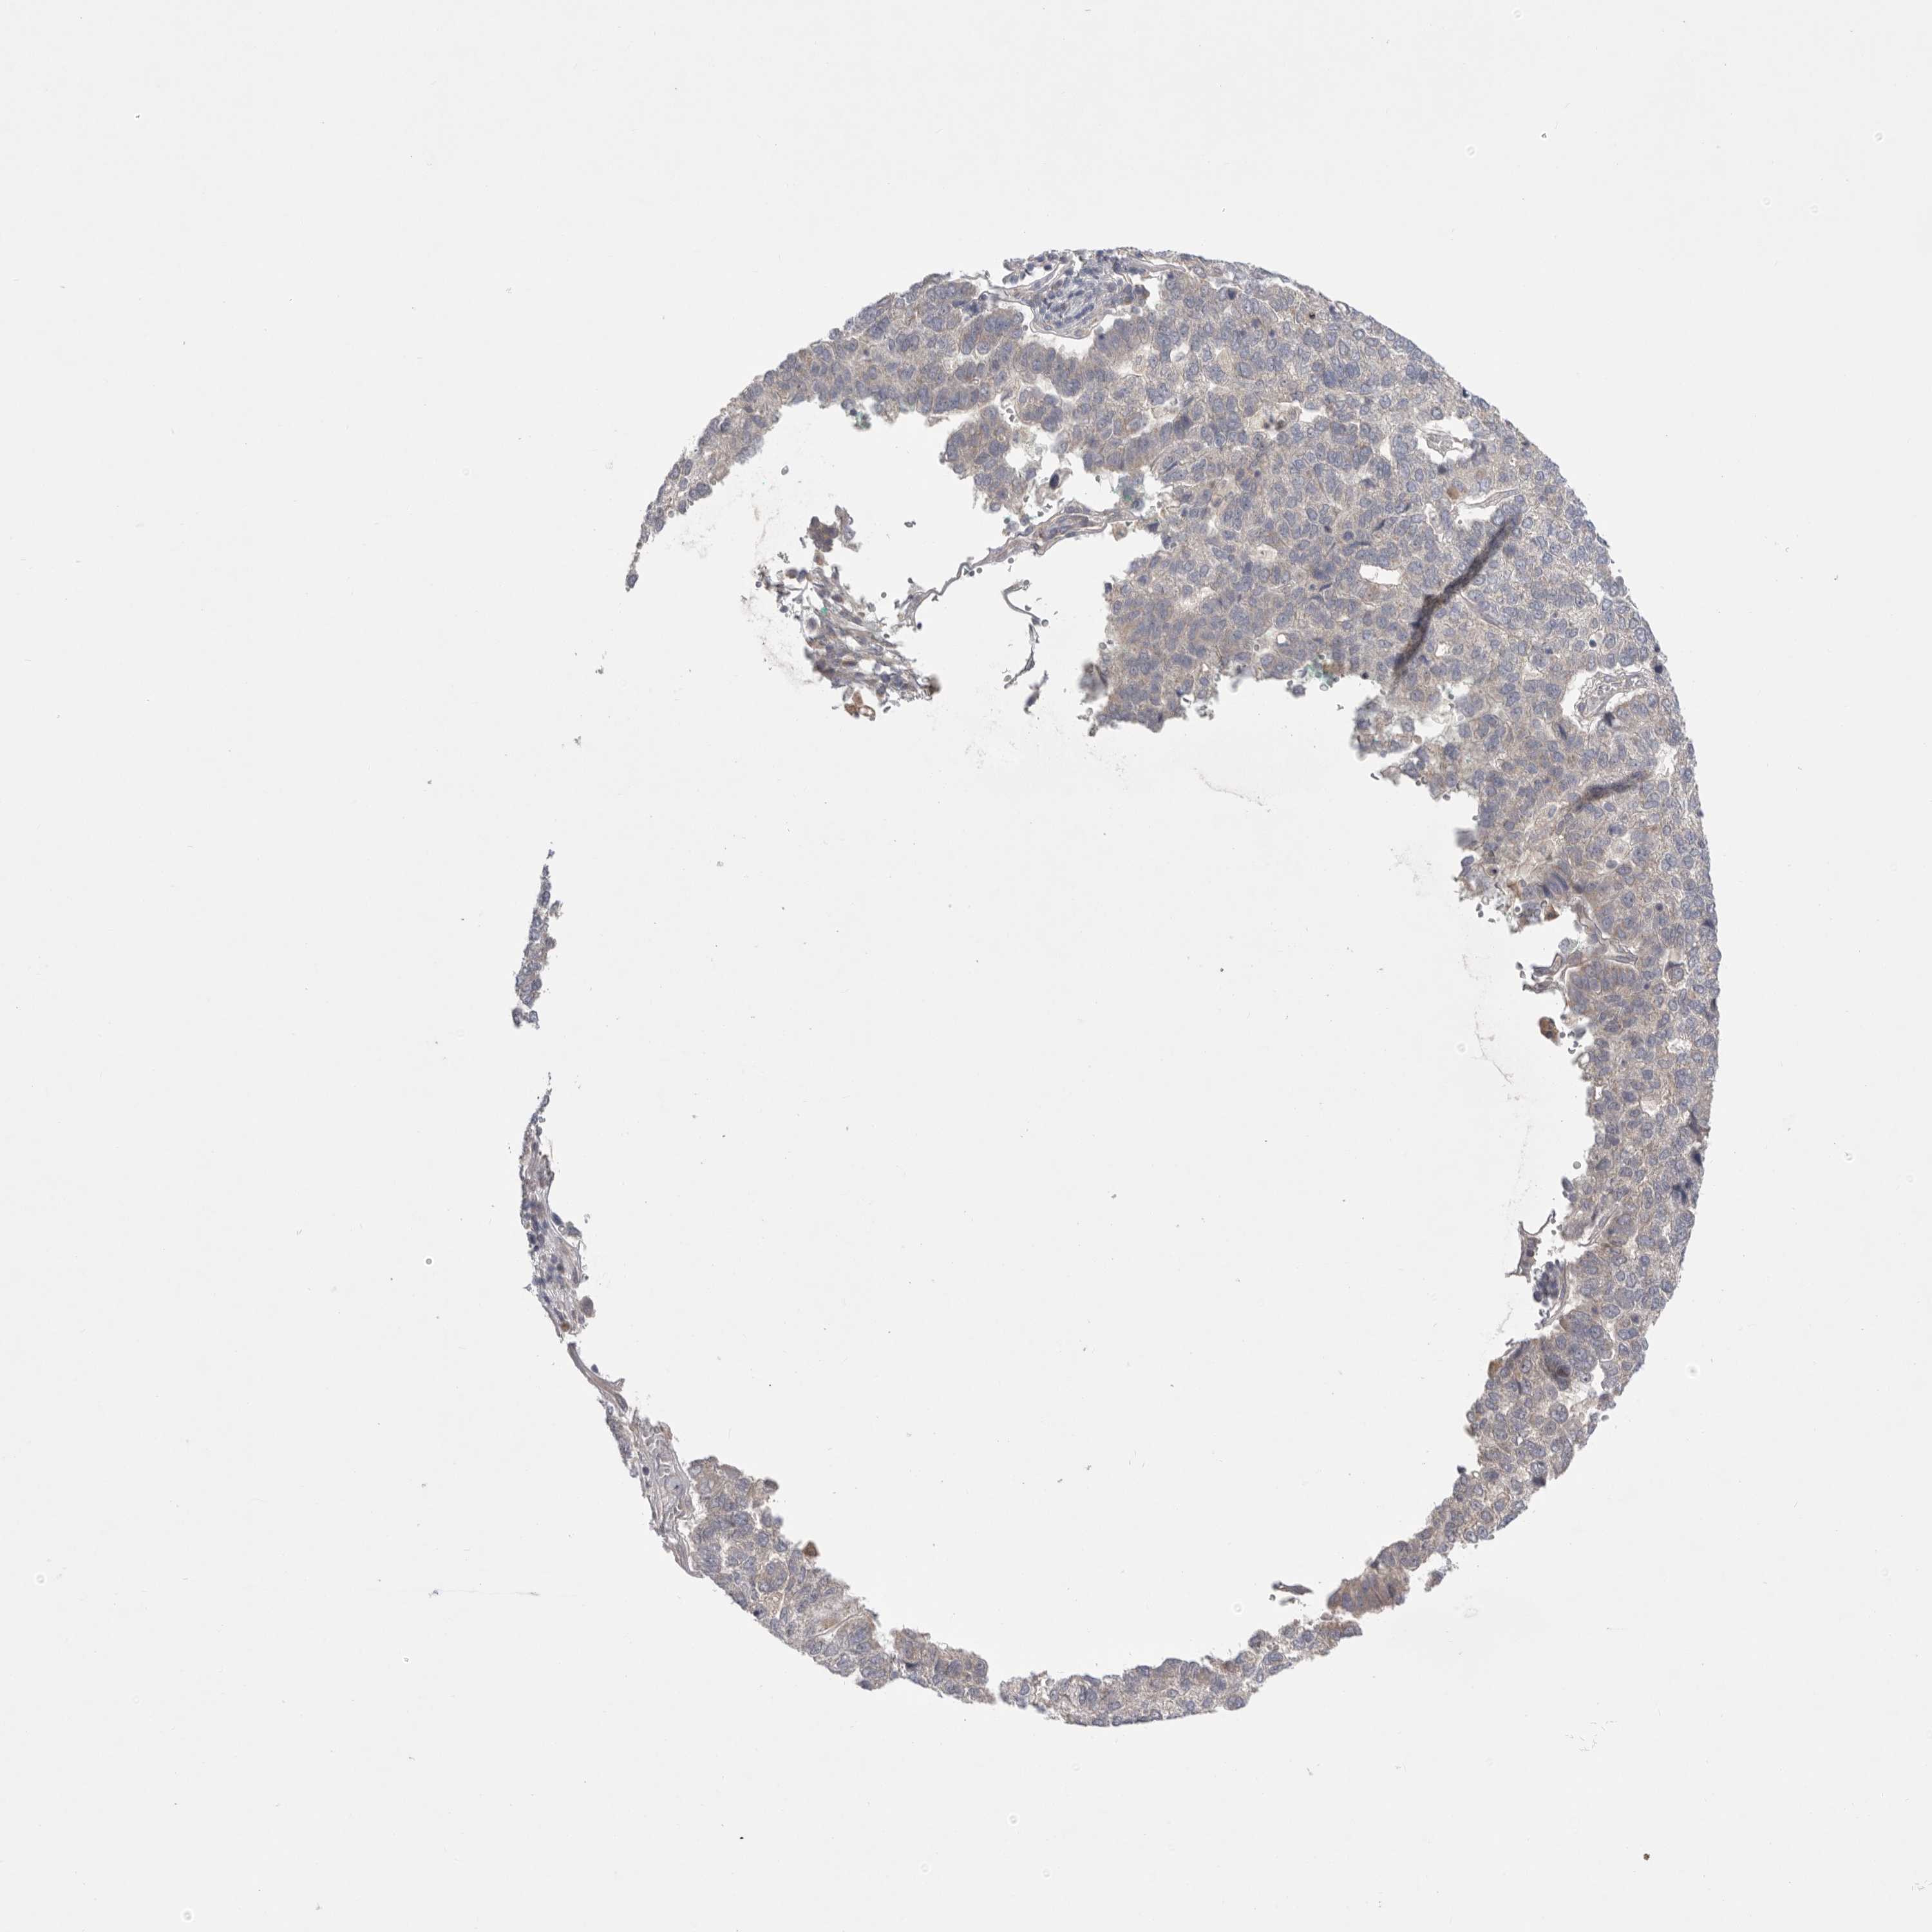

PANCREATIC CANCER - Protein expressioni

A mouse-over function shows sample information and annotation data. Click on an image to view it in a full screen mode. Samples can be filtered based on level of antibody staining by selecting one or several of the following categories: high, medium, low and not detected. The assay and annotation is described here.

Note that samples used for immunohistochemistry by the Human Protein Atlas do not correspond to samples in the TCGA dataset.

Antibody stainingi

Antibody staining in the annotated cell types in the current human tissue is reported as not detected, low, medium, or high, based on conventional immunohistochemistry profiling in selected tissues. This score is based on the combination of the staining intensity and fraction of stained cells.

Each image is clickable and will lead to virtual microscopy that enables deeper exploration of all samples and also displays staining intensity scores, fraction scores and subcellular localization as well as patient and tissue information for each sample.

Antibody HPA027124

Antibody HPA027130

Staining

High

Medium

Low

Not detected

Intensity

Strong

Moderate

Weak

Negative

Quantity

>75%

75%-25%

<25%

None

Location

Nuclear

Cytoplasmic/membranous

Cytoplasmic/membranous,nuclear

Adenocarcinoma, NOS